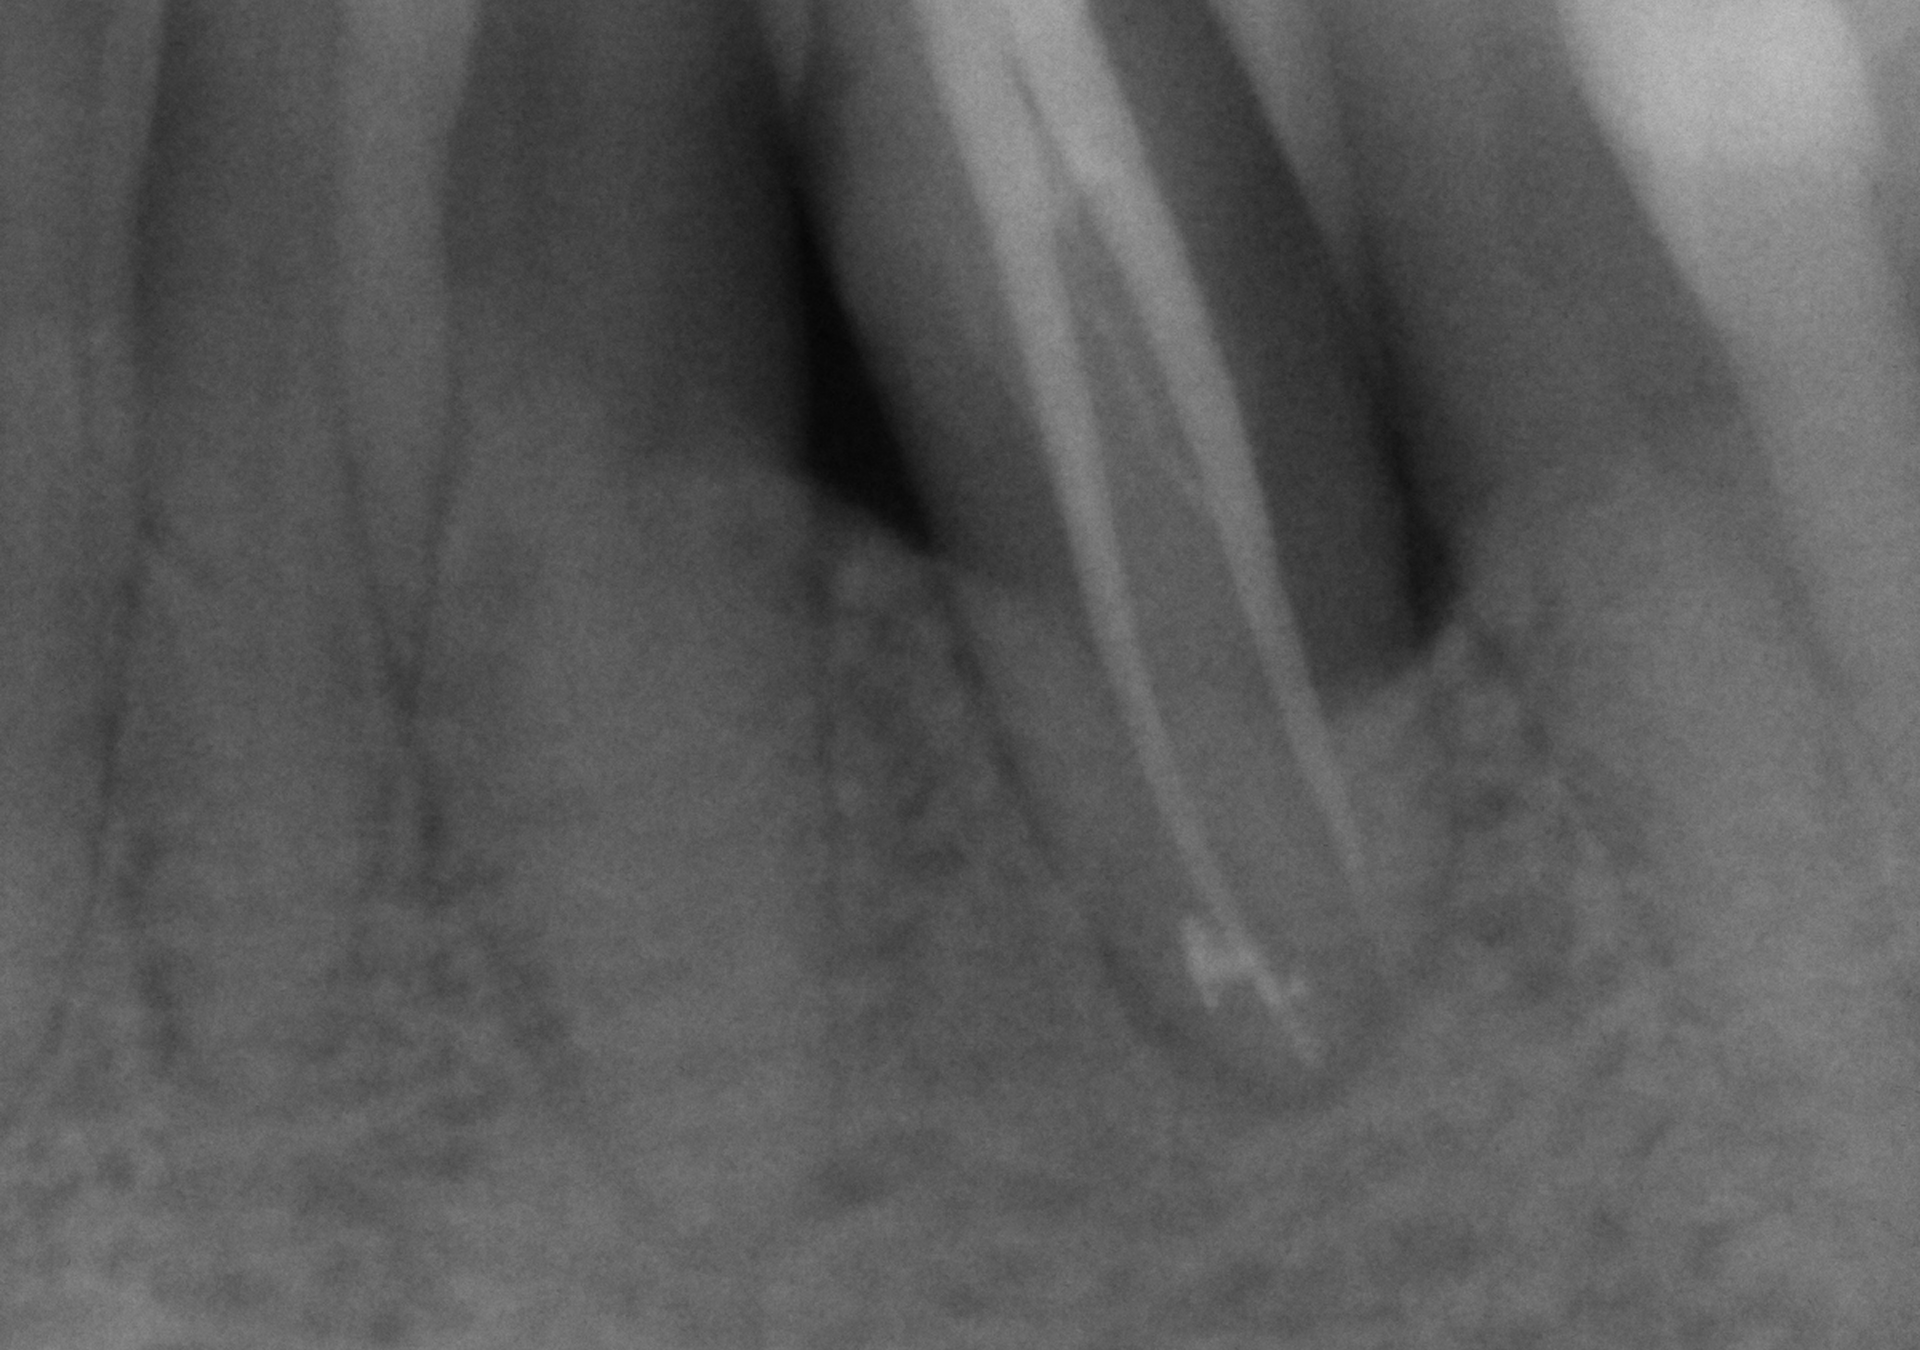

- Amplia experiencia en tratamientos de endodoncia para resolver casos de alta dificultad.

- Diagnóstico y seguimiento con CBCT para analizar con exactitud los casos evaluados.